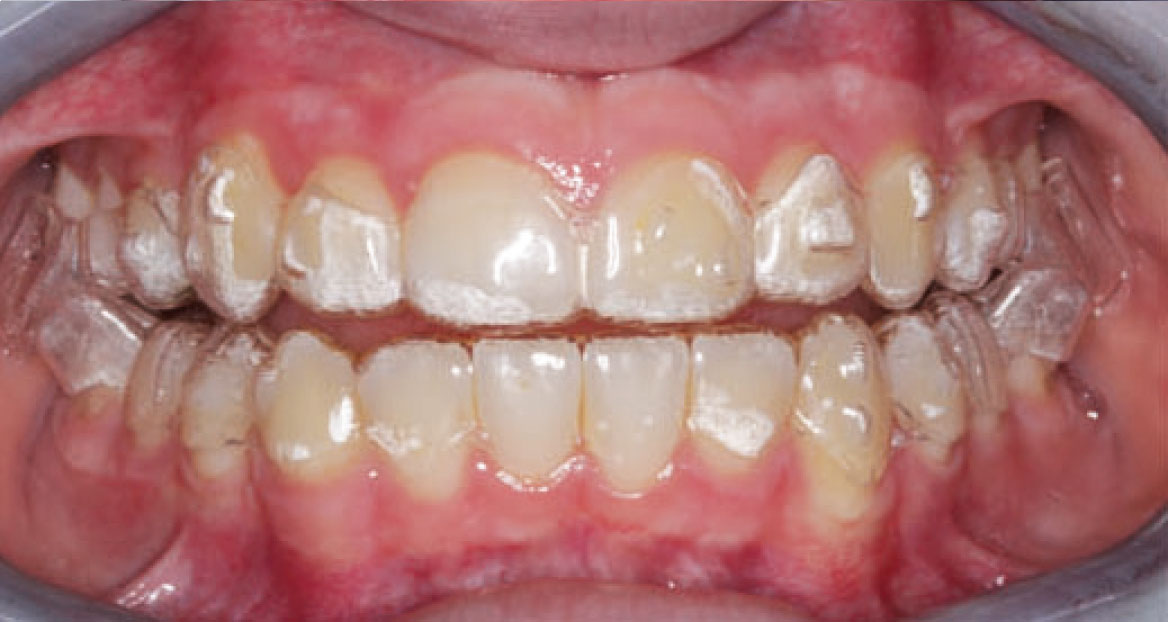

Dall’esame obiettivo intra orale si osservava una seconda classe canina destra e sinistra, una seconda classe molare destra e sinistra, e un diametro inter-canino e inter-molare ridotto sia in riferimento al mascellare superiore sia al mascellare inferiore (fig. 3A-3E).

A seguito del trattamento è stato osservato un miglioramento dell’igiene orale (fig. 5).

In seguito, il paziente è stato monitorato periodicamente sia dal reparto di ortodonzia che dal reparto di igiene orale a causa della sua storia clinica di cariorecettività inziale (fig. 8, 9).